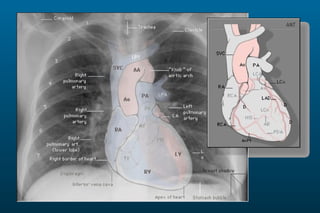

1) The posterior-anterior (PA) view is the standard and most reliable technique for a chest x-ray. It allows detection of air under the diaphragm. 2) A lateral view helps localize infiltrates and evaluate the cardiomediastinal silhouette, effusions, and left atrial dilation. 3) An anterior-posterior (AP) view is used when a patient is too ill to be transported, but image quality is poorer and structures may appear enlarged compared to a PA view.